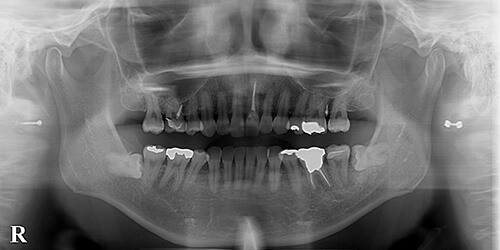

【治療前】

写真では分かりにくいですが、左下7(第2大臼歯)が垂直的に破折しており保存困難ですが、その後ろに水平埋伏智歯が確認できます。